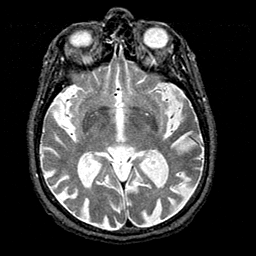

Tour 1: Next/Previous/Start: At this level, there are several small white foci in the basal forebrain. These are normal, and represent perivascular spaces of the lenticulostriate arteries. When more prominent, they may be misidentified as lacunar infarcts.